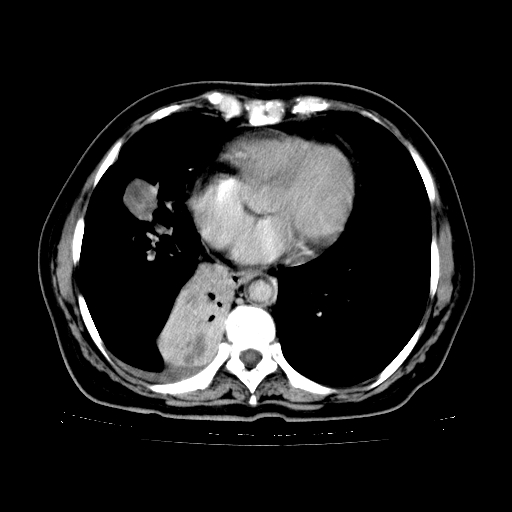

女,70岁,咳嗽、咳痰一个月,低热一周。

1.左上肺结核,部分纤维化。右肺中下叶部分肺不张,内见液化、坏死及点状钙化,右中下叶支气管壁增厚、管腔狭窄,见多个点状钙化,结合临床考虑支气管内膜结核,建议痰检查抗酸杆菌并参考血沉。两肺多个小圆点状高密度灶,境界模糊,多考虑结核肺内播散。但本人年龄较大首先应支气管镜检以除外右肺癌。

2.胸主动脉夹层。